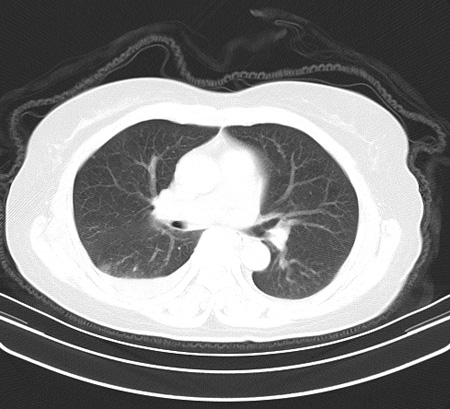

以下是引用余辉在2009-2-19 20:10:00的发言:[br]多考虑急性感染性病变,右中叶尚可见多枚小斑片状影,多为化脓性肺炎,双侧胸腔积液

以下是引用随光逐影在2009-2-19 20:33:00的发言:[br]1)考虑右肺炎症;建议抗炎治疗后复查。2)双侧胸腔积液(以右侧为甚)。

以下是引用花凤凰在2009-2-19 20:46:00的发言:[br]病人有发热,胸痛急性起病,主要病变位于右肺中叶外侧段,呈楔行改变,位于外带胸膜下,考虑为肺梗塞可能!!!!!!!!!!!!!!!!!!!!!!!!!!!!!!!!!!!